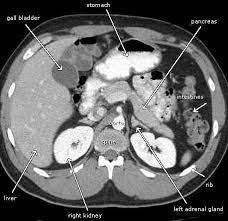

The abdominal CT scan, a non-invasive imaging procedure, offers a detailed view of the abdominal organs. It has the remarkable ability to diagnose a range of conditions, from kidney stones to tumors, providing crucial information that can guide treatment decisions. For Meena, it was a beacon of hope in a sea of uncertainty.